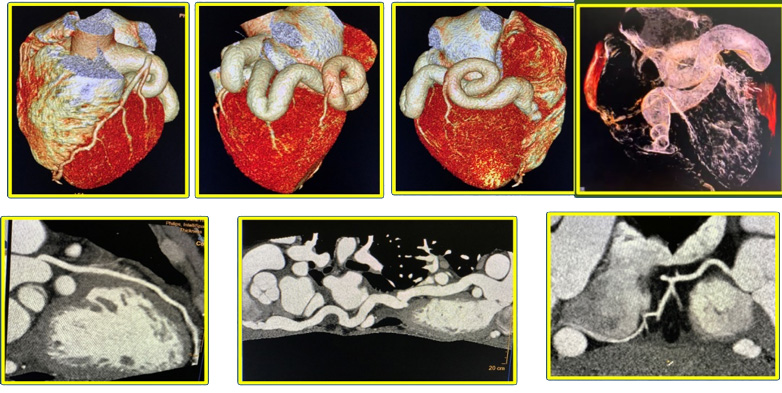

- La CAF (Fistula arterial coronaria) es una rara anomalía, con una incidencia diagnosticada por angiografía de 0.02%, incrementando con angiotomografia coronario a 0.9%, tiene un curso clínico variable, que va desde la ausencia de síntomas hasta graves complicaciones: IAM, ICC, arritmia y endocarditis en adultos, dependiendo de la extensión de la derivación.

- La angio TC Coronaria gatillada con EKG, permite la reconstrucción 3D, evaluando en forma precisa la anatomía compleja, incluyendo el sitio de origen, los sitios de drenaje, además de las anomalías asociadas.

- Esta información es fundamental para la planificación terapéutica, toma de decisiones clínicas y para obtener adecuados resultados.

Conclusión:

Mediante la presentación de este caso complejo, lo hemos evaluado por imagen multimodal: Ecocardiograma transtorácico, Angio TC Coronaria, y Resonancia Magnética Cardiaca, que nos permitieron establecer mediante los hallazgos morfofuncionales, fisiopatológicos y clínicos, que la fistula arterial coronario cavitaria de este paciente era candidato a cierre quirúrgico , con resolución exitosa de la patología.